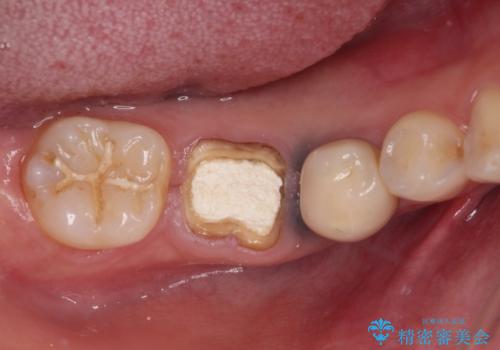

- 他院で治療を開始したものの抜歯が必要と言われ、何とか残せないものかとのことで来院された患者様です。

下顎大臼歯は歯冠部分が残っておらず、保存が難しいように思えましたが、まずは根管治療を行った上で補綴治療を行うこととしました。

上顎臼歯は、おそらく銀歯を外して仮詰めされていたため、再度形を整え、セラミックインレーにて修復治療を行うこととしました。